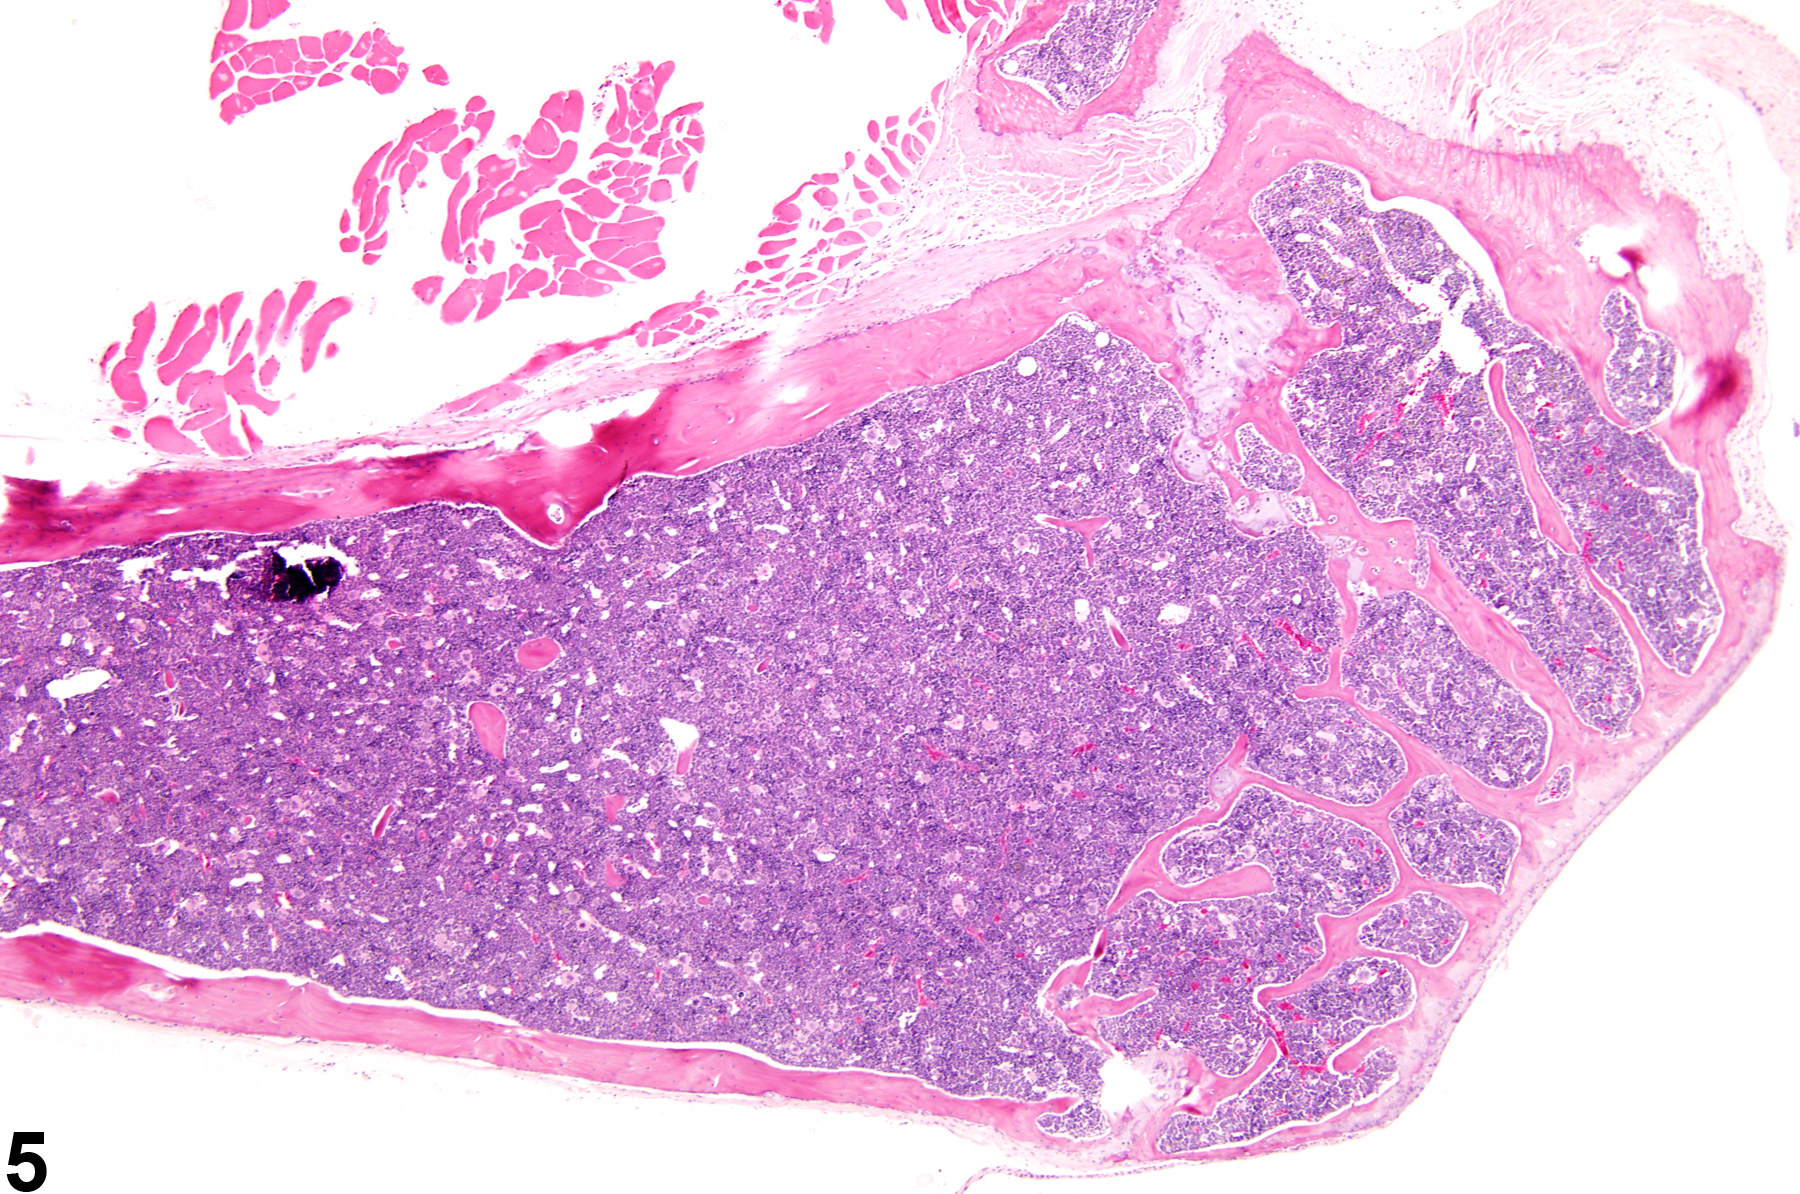

Hypercellularity of the bone marrow is recorded in treated animals when there is an increase in hematopoietic cells relative to adipocytes compared with concurrent controls (Figure 2, Figure 4, and Figure 5). Hypercellularity may occur as a nonspecific or direct (e.g., with cytokine administration) response to compound administration but more commonly is due to a regenerative response as a consequence of decreases in peripheral blood cells, recovery from a xenobiotic-induced bone marrow injury, or inflammation. For example, hypercellularity may be secondary to sepsis or a result of blood loss, hemolytic anemia or platelet consumption/destruction. Stimulation to produce more of one cell line can cause increased production of other cell lines, causing an overall increase in bone marrow cellularity. With marked hypercellularity, hematopoietic cells may fill the entire marrow space, even extending through the nutrient foramina.

Bone marrow in a control female F344 rat from a subchronic study.